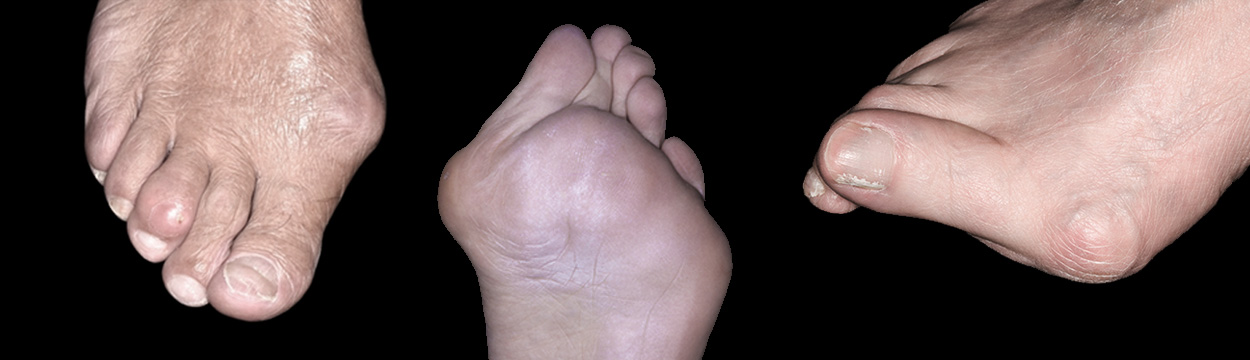

부모님이 무지 외반증을 가지고 있을 때, 발볼이 넓은 유연한 발을 가지고 있을 때 무지외반의 발병이 흔하며,

청소년기에 보이는 무지 외반증은 유전적인 요인 때문이라고 볼 수 있습니다.

뼈의 변형이 원인이기 때문에 교정기 등은 효과가 없는 것으로 알려져 있으며,

증상 호전을 위해 발볼이 넓은 신발을 신는 등의 교정을 먼저 시도해볼 수 있습니다.

만약 증상이 심하고 호전되지 않을 때 수술적 치료를 고려하게 됩니다.